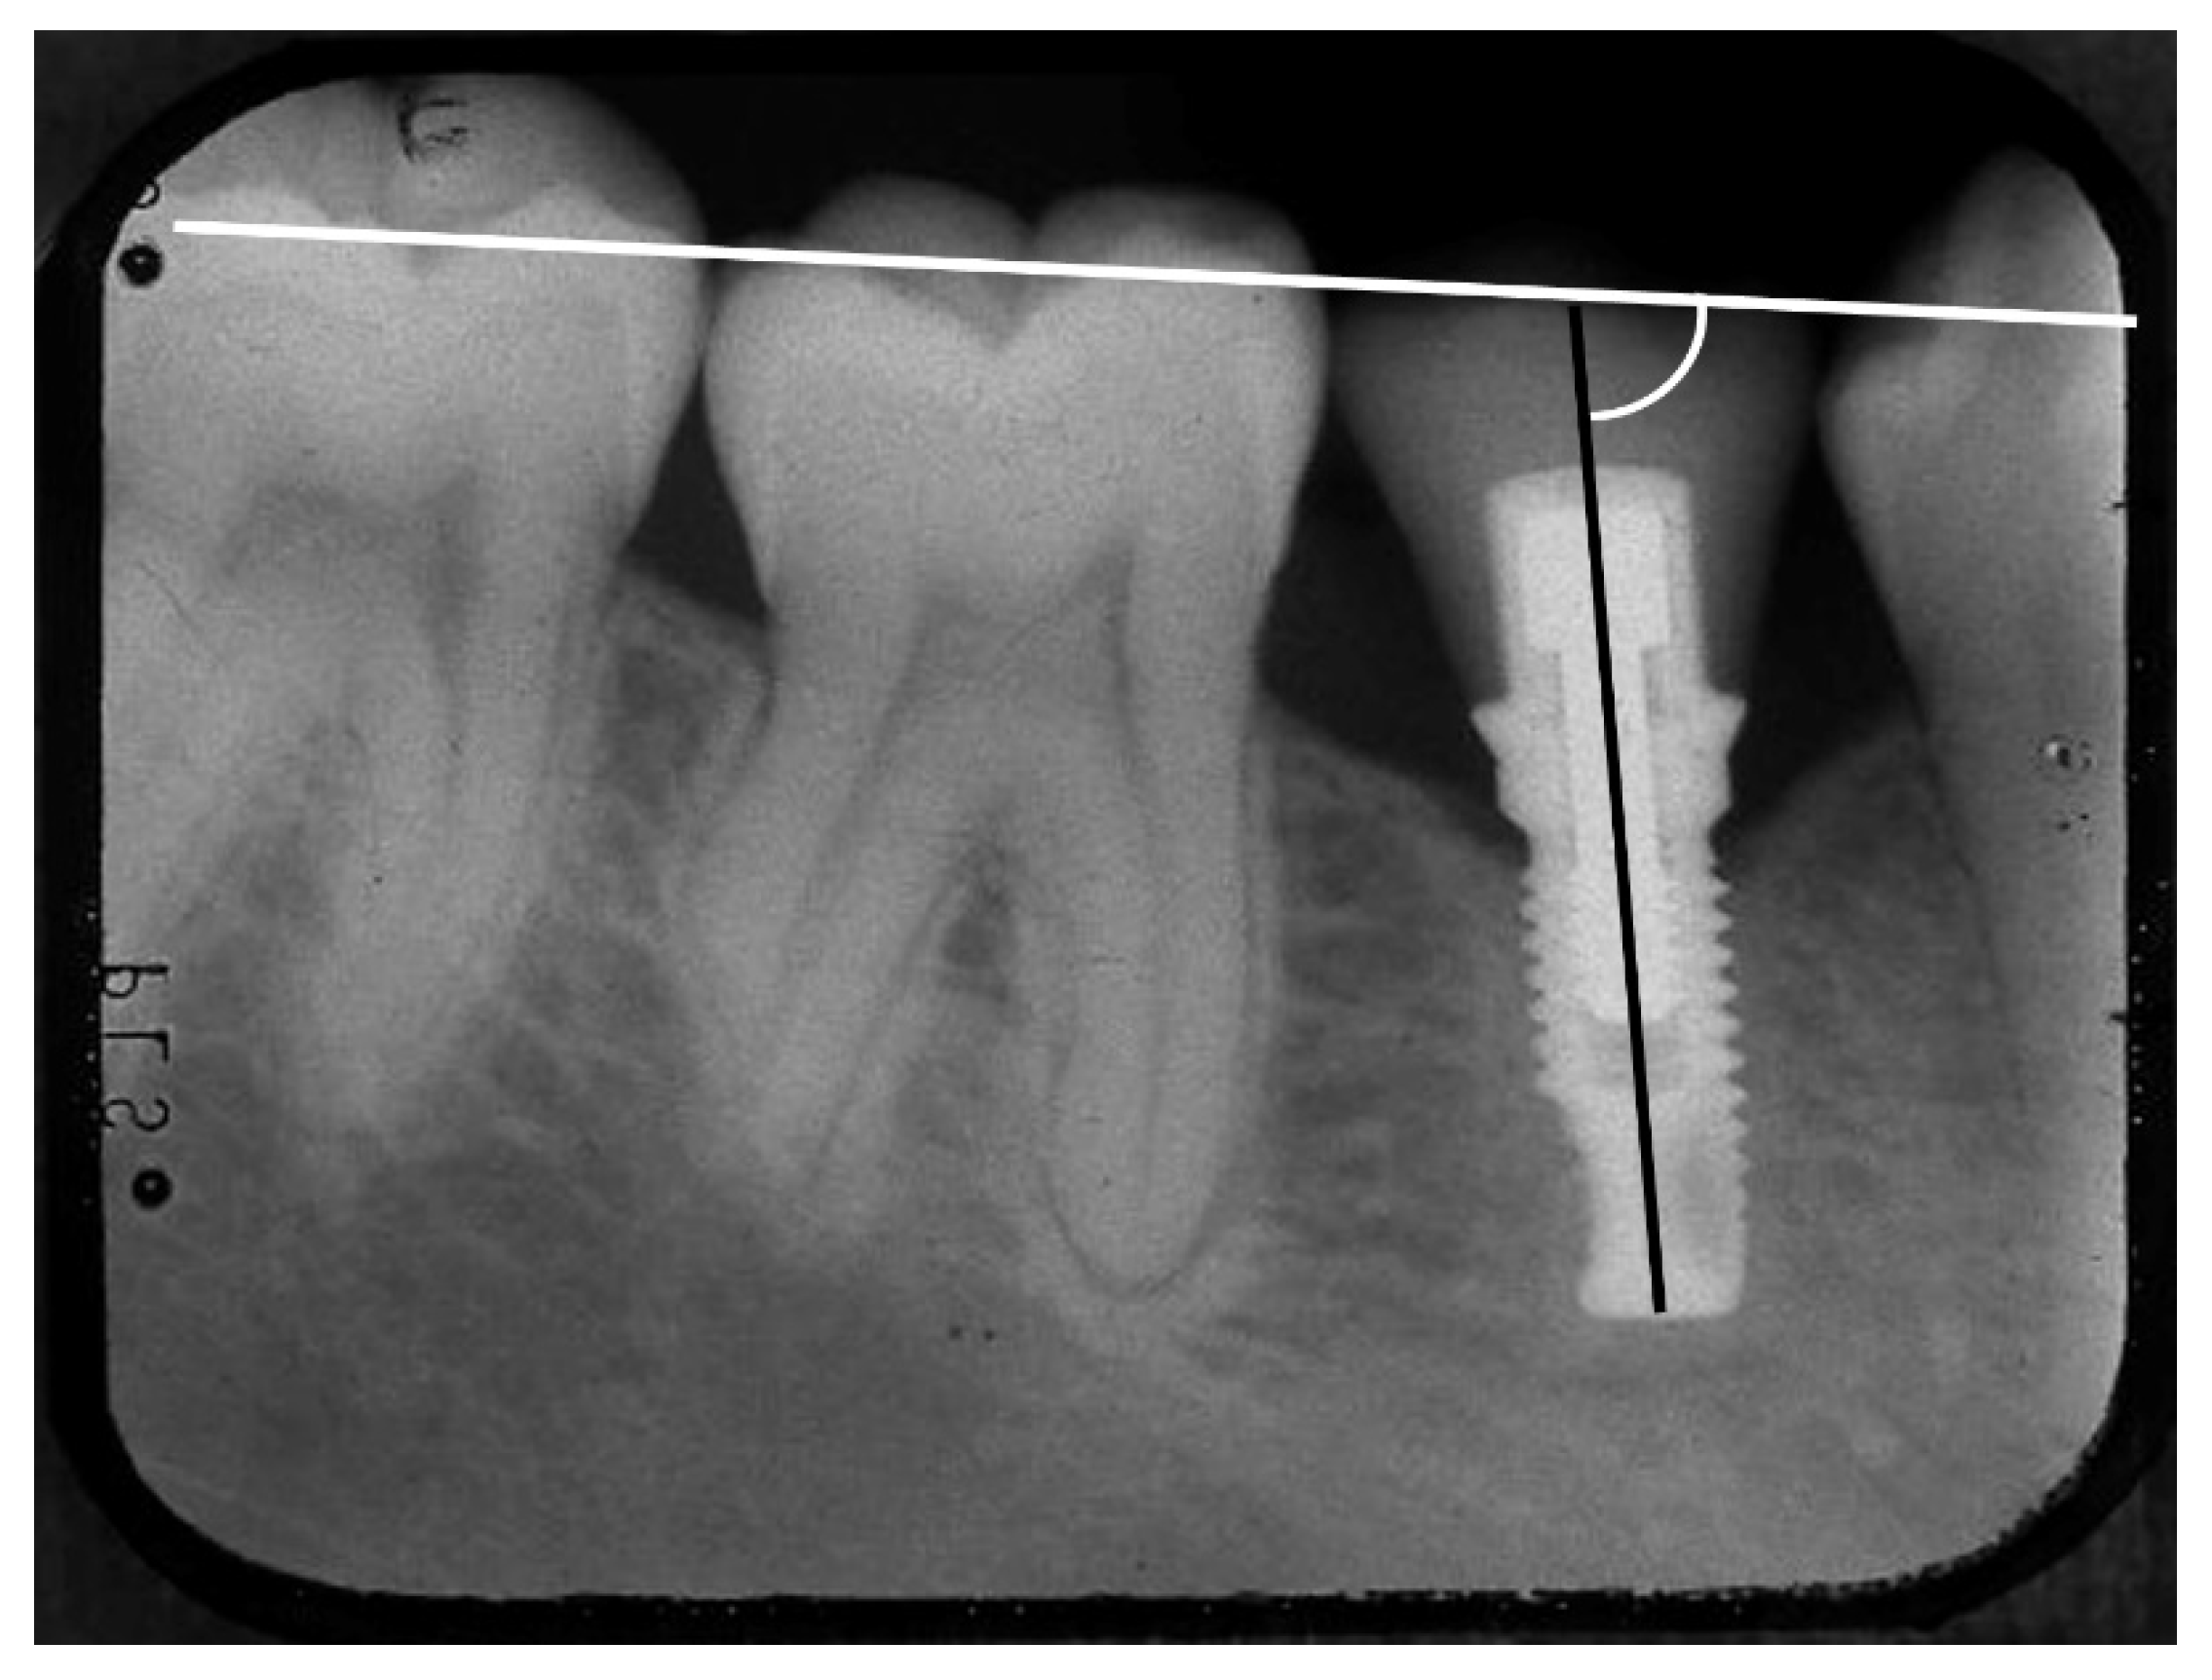

2.6. Radiological Evaluation